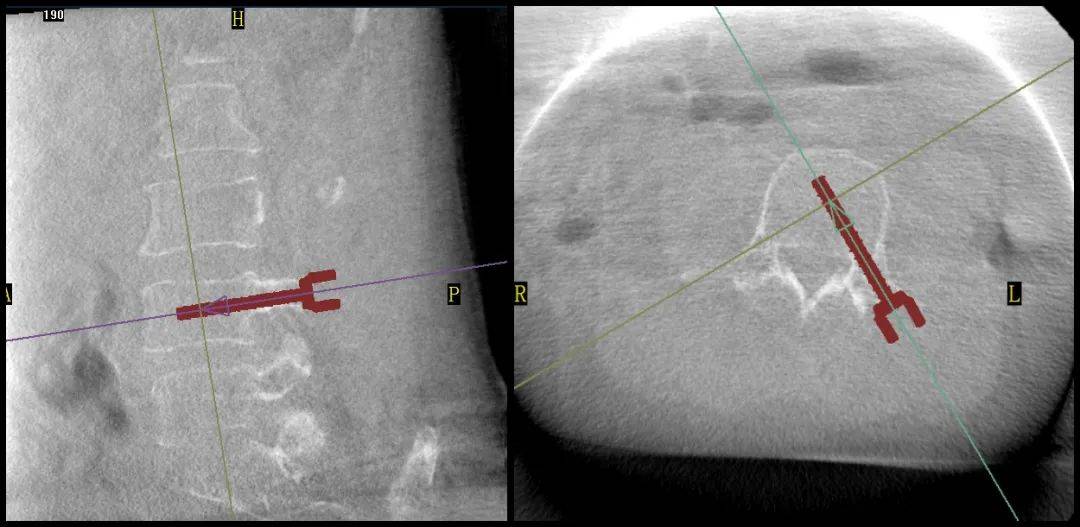

手術過程中,普愛醫(yī)療平板三維C形臂為患者拍攝了清晰的三維影像,醫(yī)生基于影像完成了兩個節(jié)段的穿刺路徑規(guī)劃。

普愛醫(yī)療品牌骨科手術機器人的機械臂憑借高精度導航能力,引導醫(yī)生一次性精準穿刺,憑借超大內傾角度單通道抵達椎體中央位置,達到雙通道的骨水泥彌散效果,成功完成兩節(jié)跨節(jié)段椎體的骨水泥注入。